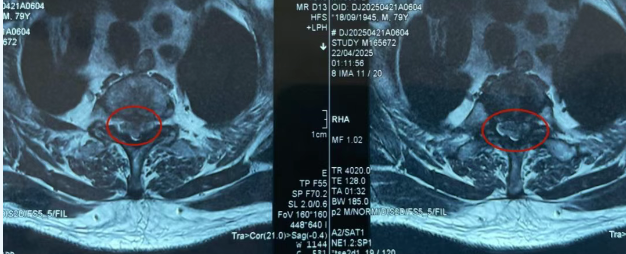

一个月前,李大爷突发双腿无力、无法行走,甚至咳嗽时全身如"过电"般,经检查确诊为胸椎1-2节腹侧严重突出并钙化。该部位位于脊柱"高位区",紧邻脊髓和胸腔重要神经,且突出物生长于脊髓腹侧(前方),传统手术需绕开脊髓操作,稍有不慎可能导致瘫痪、呼吸功能障碍等严重后果。加之患者年近八旬,心肺功能较弱,麻醉与术后恢复风险极高,当地医生权衡再三,果断推荐李大爷前来我院接受进一步治疗。

胸椎椎管本身为全脊柱最狭窄区域,腹侧椎间盘突出位于脊髓前方,需通过后路或侧方入路绕过脊髓,在脊髓前方仅有的狭窄间隙内完成减压,对术者技术及设备要求极高。